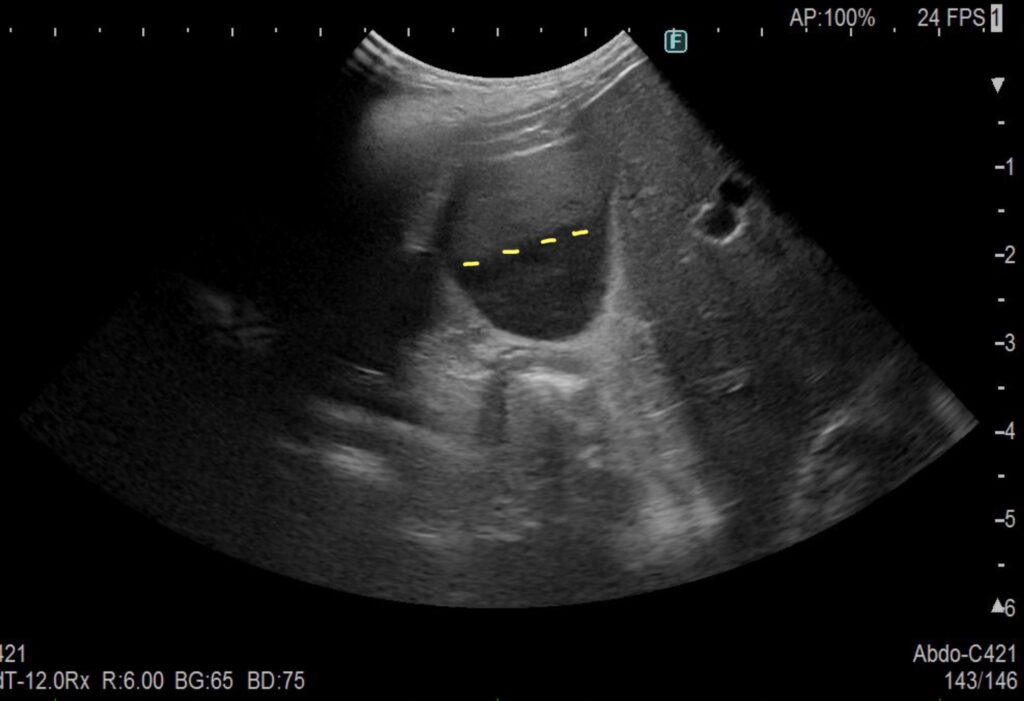

以下は犬の胆嚢のエコー画像です。

犬の正常な胆嚢

矢印の黒いところが正常な胆嚢です。

エコーで真っ黒に映るところは液体であり、胆嚢は本来、このように真っ黒に映ります

犬の胆泥症(可動性)

これが胆泥症の胆嚢です.

黒いところと、白いところ(グレー)の境目が、一本の線で分けられる時は、可動性の胆泥症です。

この場合は治療が必要ない胆泥症といえます。

犬の胆泥症(胆石になりかけ)

前の画像とは違い、一本の線が引けません。

これは、胆泥症から胆石になりかけている途中の状態です